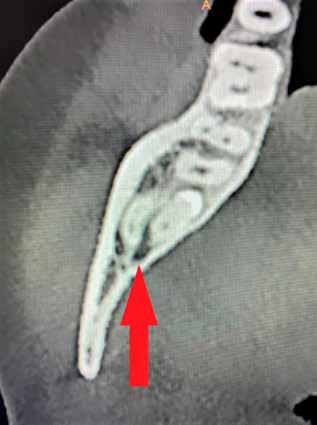

A CT metszetekben a 48-as gyökerei körbeölelik a canalis mandibularist, amelyet piros nyíllal jelöltünk a fotókon.

Szeretnék mutatni néhány ábrát az egyik bonyolult esetről, a közelmúltból. A CT-n látszik, hogy a három gyökér teljesen „körbenőtte” az ideget. Van olyan frontális metszeti kép, ahol csak a gyökerek vannak a nervus körül, ezen a szakaszon egyáltalán nincs meg a csontos fala a canalisnak. Szeparációs technikával, viszonylag könnyen, minimális traumával, szövődménymentesen sikerült eltávolítani a fog minden részét. A várakozásnak megfelelően, a beteg nem számolt be paraesthesiáról.